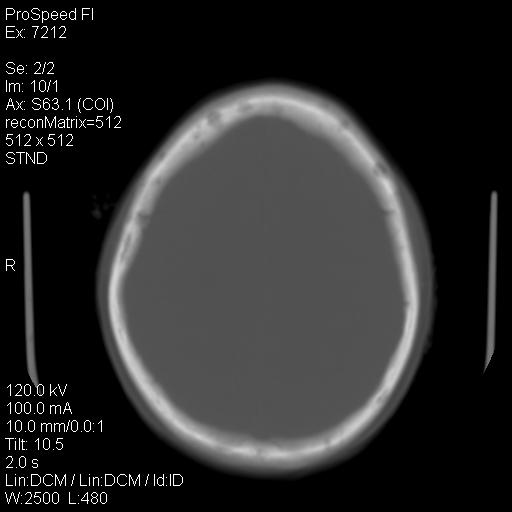

标题: CT18636:F 44Y,头痛三个月,左侧肢体麻木一周。临床诊断, [打印本页]

标题: CT18636:F 44Y,头痛三个月,左侧肢体麻木一周。临床诊断,

额顶骨多发穿凿样骨缺损区,不排除骨髓瘤等改变,进一步检查。

额顶骨多发穿凿样骨缺损区,不排除骨髓瘤或嗜酸性肉牙肿等改变,进一步检查。

1)考虑左侧额部慢性硬膜下血肿(或硬膜下积液)。2)颅骨骨髓瘤不排除;建议行进一步检查。

2)颅骨骨髓瘤不排除;建议行进一步检查。

1)右侧半卵圆中心腔隙性脑梗塞。2)考虑左侧额部慢性硬膜下血肿(或硬膜下积液)。3)颅骨骨髓瘤不排除;建议行进一步检查。